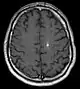

Diagnosis is generally made by magnetic resonance imaging (MRI), particularly using a specific imaging technique known as a gradient-echo sequence MRI, which can unmask small or punctate lesions that may otherwise remain undetected. These lesions are also more conspicuous on FLAIR imaging compared to standard T2 weighing. FLAIR imaging is different from gradient sequences. Rather, it is similar to T2 weighing but suppresses free-flowing fluid signal. Sometimes quiescent CCMs can be revealed as incidental findings during MRI exams ordered for other reasons. Many cavernous hemangiomas are detected "accidentally" during MRIs searching for other pathologies. These "incidentalomas" are generally asymptomatic. In the case of hemorrhage, however, a CT scan is more efficient at showing new blood than an MRI, and when brain hemorrhage is suspected, a CT scan may be ordered first, followed by an MRI to confirm the type of lesion that has bled.[19] Sometimes the lesion appearance imaged by MRI remains inconclusive. Consequently, neurosurgeons will order a cerebral angiogram or magnetic resonance angiogram. Since CCMs are low flow lesions (they are hooked into the venous side of the circulatory system), they will be angiographically occult (invisible). If a lesion is discernible via angiogram in the same location as in the MRI, then an arteriovenous malformation (AVM) becomes the primary concern.